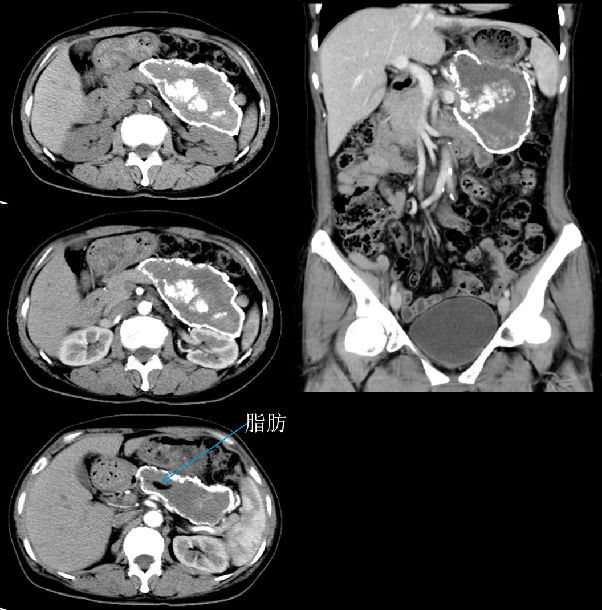

女,54岁,间断背痛1月,加重2天,外院CT发现腹膜后巨大占位

影像学所见(上图)胰腺体尾部可见一不规则肿块影,大小约167.5px×312.5px×252.5px,边界清楚,边缘可见厚薄不一的环形钙化,内部密度不均匀,主体以软组织密度为主,平均CT值约39HU,增强扫描未见强化,其内另见多发点状、团块状钙化密度影及条样脂肪密度影;胰腺头颈部密度均匀,未见异常强化灶。

术前影像学印象: 畸胎瘤? 错构瘤?

本病例术前CT病变除边缘钙化,病变内点片状钙化外,病变内可见条片状脂肪组织,故术前考虑畸胎瘤或错构瘤可能。术前穿刺及术后病理提示病变内为退变坏死物,未见健活细胞成分,综合考虑坏死性胰腺炎可能,病变内脂肪成分考虑腹腔内脂肪组织卷入可能。